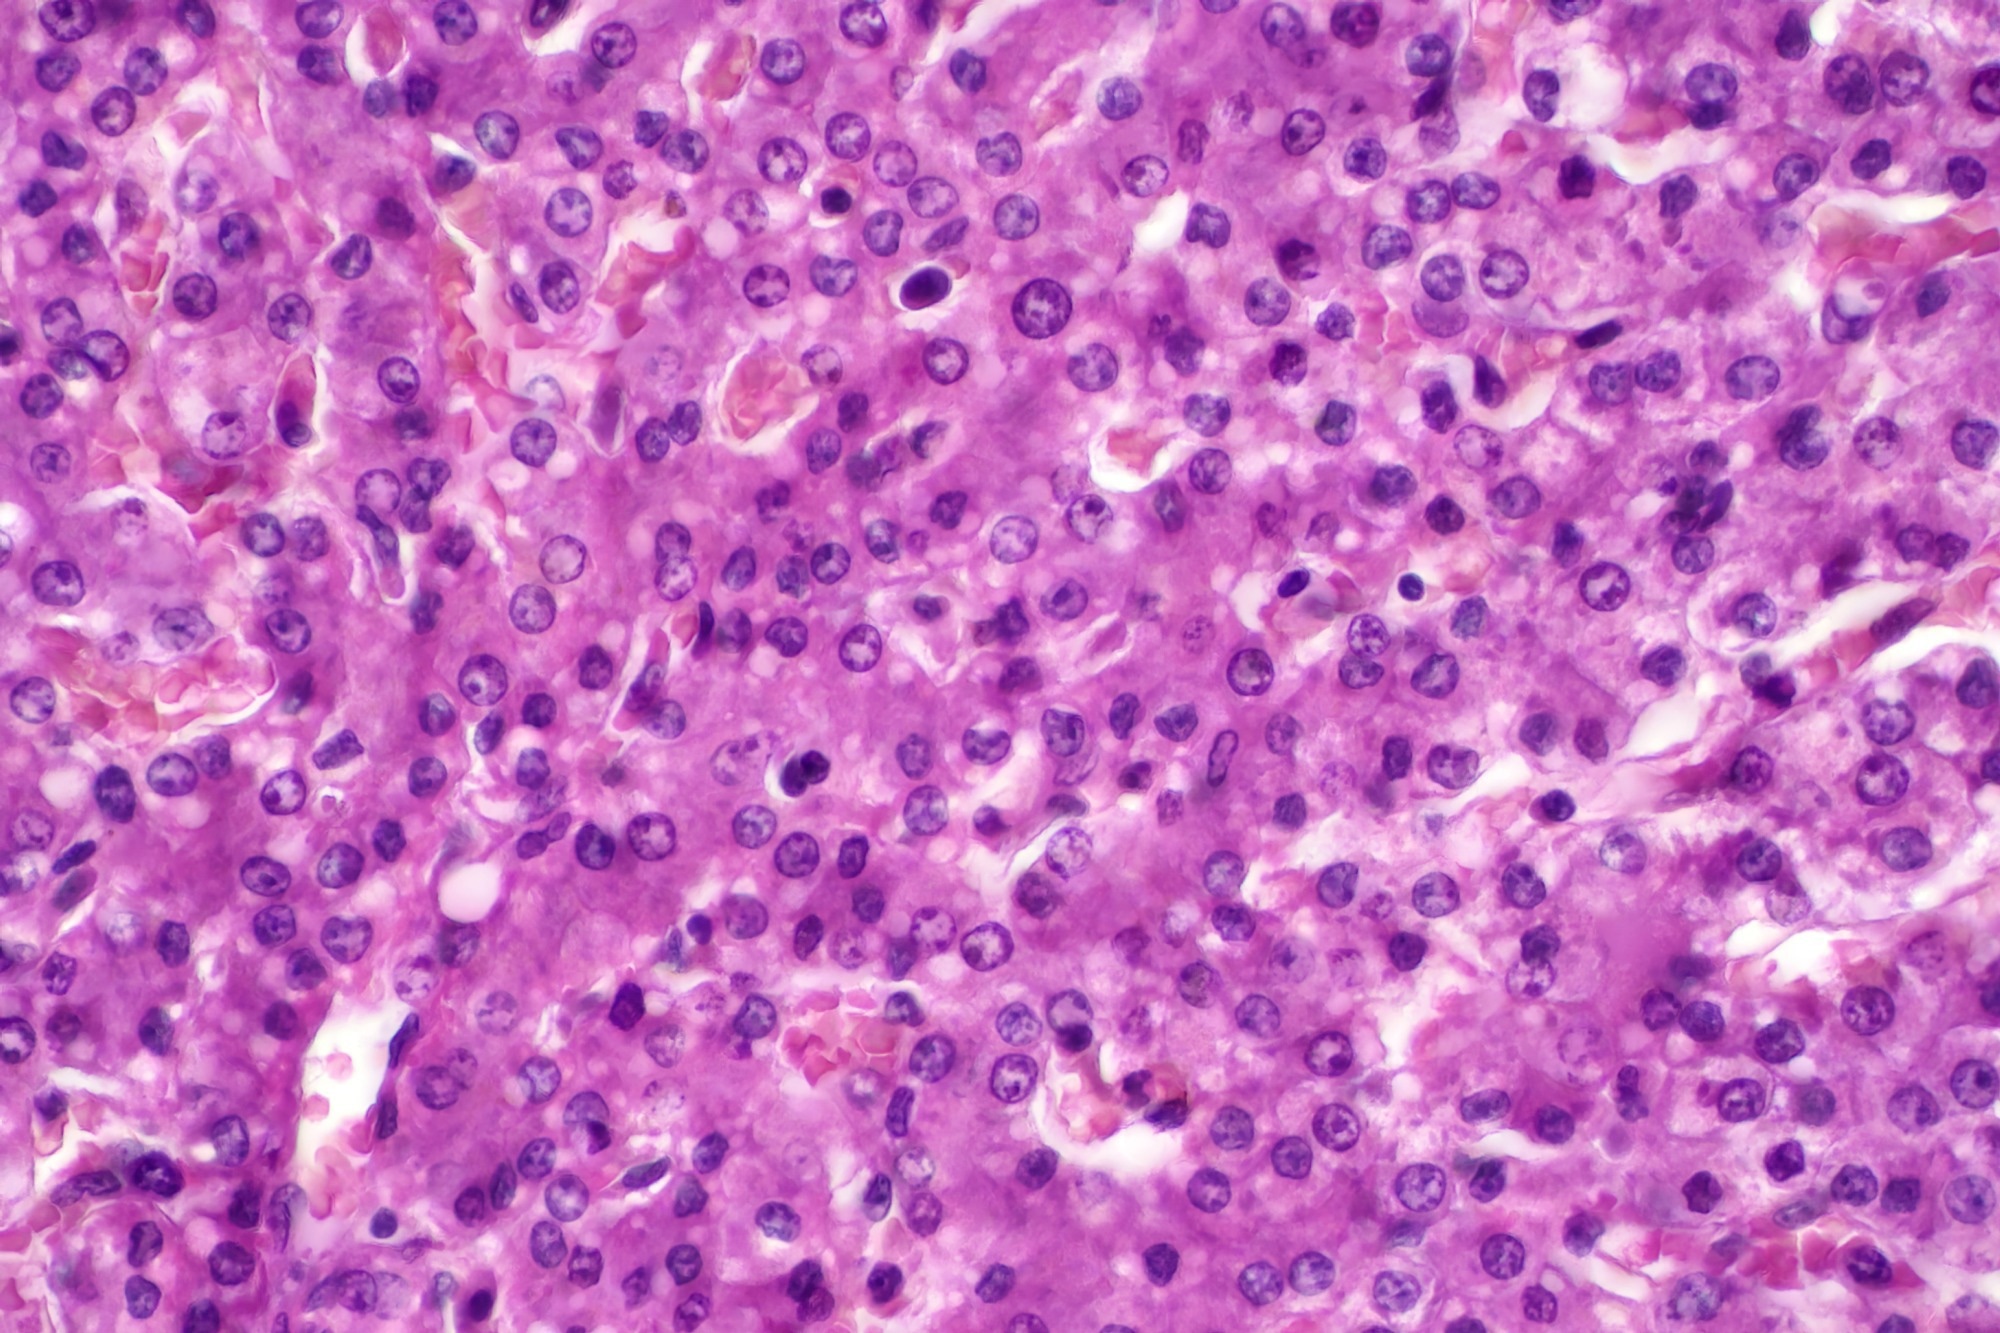

Image Credit: Choksawatdikorn/Shutterstock.com